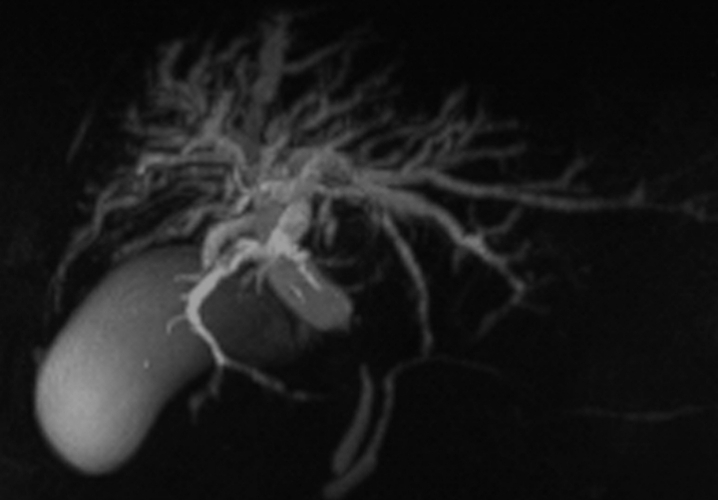

TDM hépatique avec injection de contraste

Publié par : Kamal nadifi

Hémangiome caverneux du foie : TDM hépatique avec injection de contraste.

Publié par : Kamal nadifi